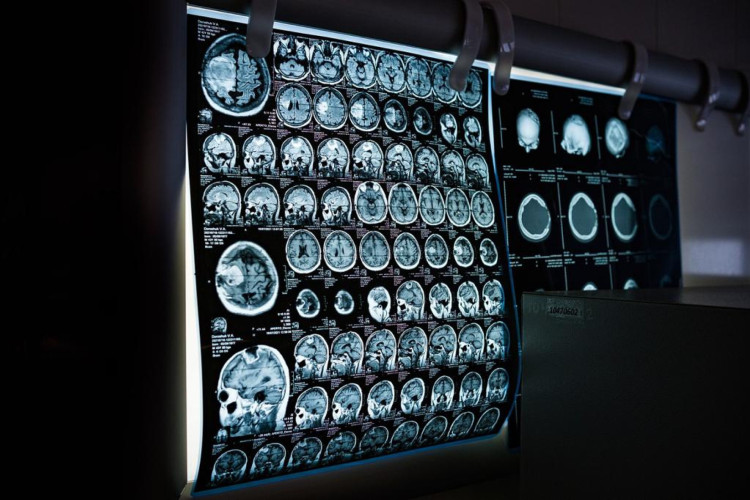

Um beneficiário da operadora de saúde Hapvida denuncia que teve um procedimento de emergência negado pela rede em Fortaleza. O psicológo Jeferson Weyne Maciel Filho, 38, solicitou uma ressonância magnética a partir de prescrição médica realizada após o diagnóstico de um cisto no cerebelo. O procedimento, no entanto, foi negado pela operadora alegando que o cliente estava em período de carência do plano.

Em janeiro, após os sintomas continuarem, uma infectologista passou uma tomografia para buscar a causa das dores. O resultado do exame apontou para um cisto gelatinoso.

A partir do exame, o psicólogo procurou um neurologista que prescreveu uma ressonância magnética, como um procedimento de urgência. O cliente buscou o plano de saúde no hospital Antônio Prudente, no bairro de Fátima, em Fortaleza, para a realização do exame, considerando o risco.